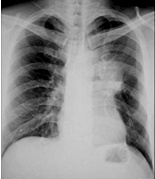

![]() | 病史:女性,39岁,胸痛伴高热、咳嗽4天。诊断: |

| ○右肺结核 | |

| ○右上肺癌 | |

| ○ 右侧肺炎 | |

| ○正常胸片 | |

| ○气胸 |